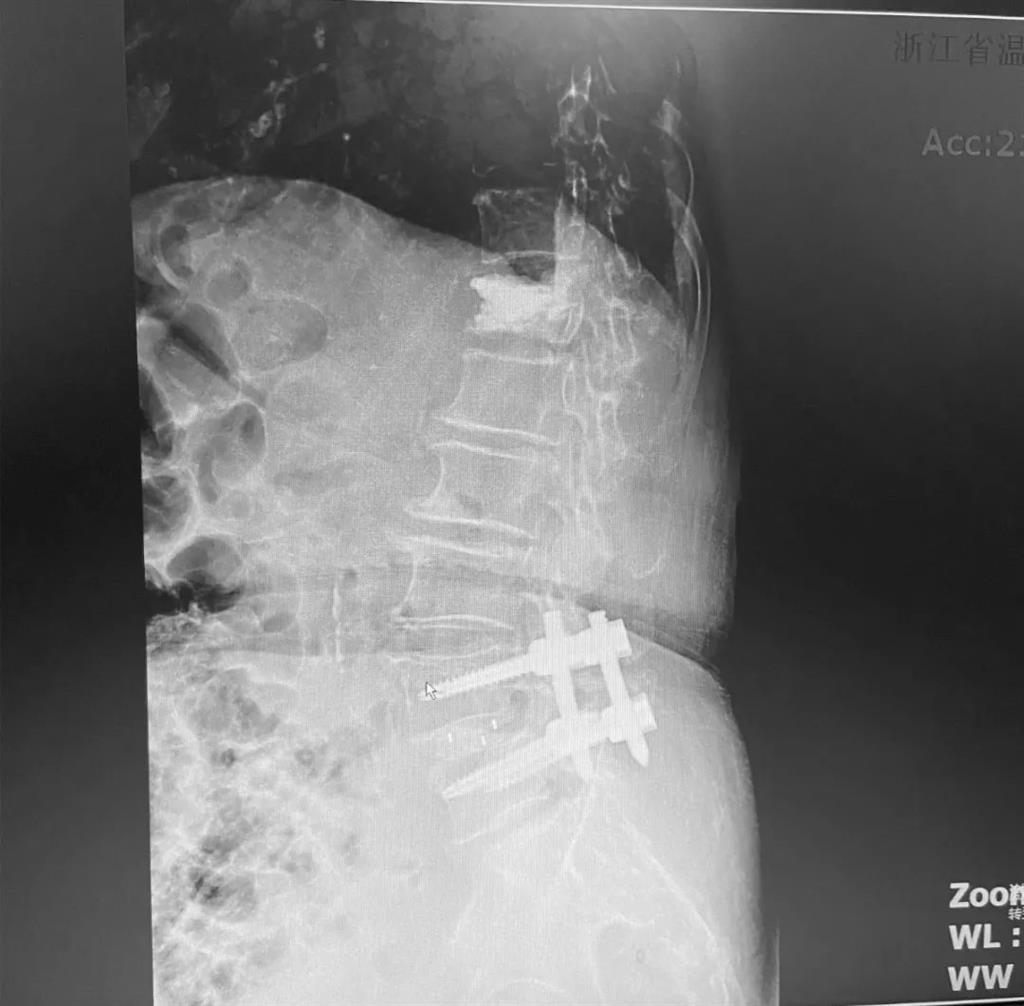

據(jù)了解,脊柱內(nèi)鏡下腰椎融合術(shù)只需要打幾個(gè)“鑰匙孔”即可完成。聽(tīng)起來(lái)是不是很簡(jiǎn)單?在脊柱內(nèi)鏡下,劉丹主任先后為患者進(jìn)行了椎管減壓、椎間盤摘除,再實(shí)施椎弓根螺釘放置、椎體植骨融合內(nèi)固定,一系列步驟有條不紊。

看似簡(jiǎn)單的幾個(gè)步驟,但實(shí)際上很復(fù)雜,需要主刀醫(yī)生有豐富的手術(shù)經(jīng)驗(yàn)和細(xì)致耐心的操作。

劉丹主任表示,傳統(tǒng)手術(shù)需要廣泛剝離脊椎兩側(cè)的肌肉,術(shù)后容易產(chǎn)生疤痕、肌肉萎縮、腰部疼痛等;術(shù)中出血多,往往需要額外輸血,另外創(chuàng)傷大的同時(shí)也容易破壞脊椎的正常結(jié)構(gòu),對(duì)于老年人、體弱的人群來(lái)講,恢復(fù)期長(zhǎng)、風(fēng)險(xiǎn)多。

而脊柱內(nèi)鏡下腰椎融合術(shù),作為目前國(guó)內(nèi)脊柱微創(chuàng)領(lǐng)域大力發(fā)展的新技術(shù),徹底改變了傳統(tǒng)開(kāi)刀椎板切除椎間植骨融合內(nèi)固定的大創(chuàng)傷現(xiàn)狀,可以在較大程度上減少對(duì)脊柱后方穩(wěn)定結(jié)構(gòu)的破壞,創(chuàng)傷小,出血少,術(shù)后恢復(fù)快。

非常適用于體質(zhì)較差不能耐受開(kāi)放手術(shù)的老年患者,且手術(shù)全程均在內(nèi)鏡監(jiān)測(cè)下進(jìn)行,能夠最大程度地避免硬膜囊和神經(jīng)根損傷,手術(shù)安全性更高。

術(shù)中只需切開(kāi)4個(gè)如“鑰匙孔”般大小的孔道